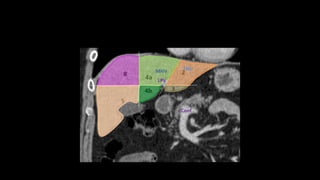

• There are eight liver segments.

• Segment IV is divided into segment IVa and IVb according to Bismuth.

• The numbering of the segments is in a clockwise manner.

• Segment I (the caudate lobe) is located posteriorly.

• It is not visible on a frontal view.

• The right portal vein divides into

anterior (supplying segments 5 and 8)

and posterior (supplying segments 6 and

7) branches.

• The left portal vein may be divided into

transverse and umbilical portions.

• The main branches of the left portal vein

originate from the umbilical portion, and

supply liver segments 2, 3 and 4